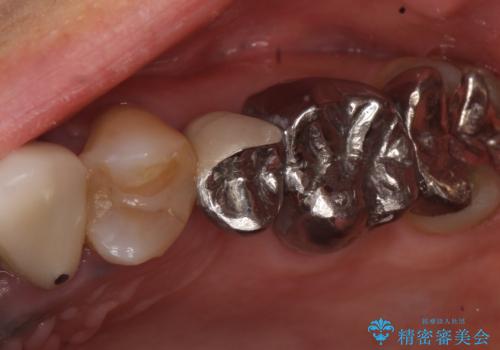

- 昔治療した左上56の延長ブリッジをきちんと治療しなおしたいといらっしゃった方の症例です。

古いブリッジを除去後、オールセラミッククラウンによる補綴を行いました。